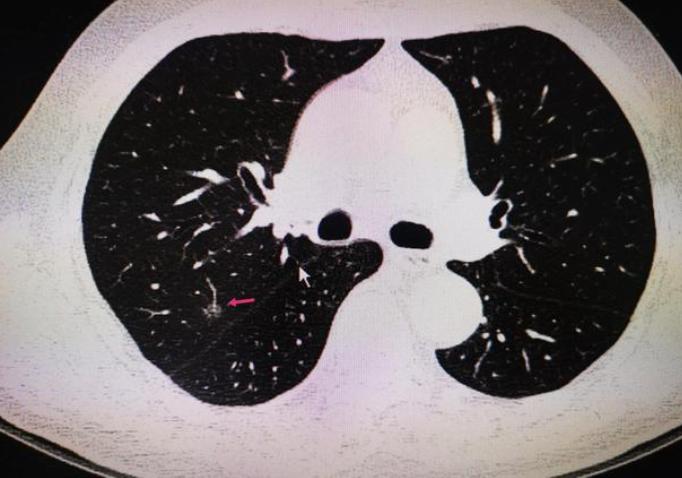

卢某开始担心起来,在朋友的陪同下,到医院进行检查,经过检查,查出肺结节,报告如下:

“距脏层胸膜0.5cm处切面见结节1,直径0.7cm,切面灰白,质中,界清;距离支气管切缘5.1cm、距脏层胸膜0.4cm处切面见结节2,大小0.5*0.7*0.7cm。”